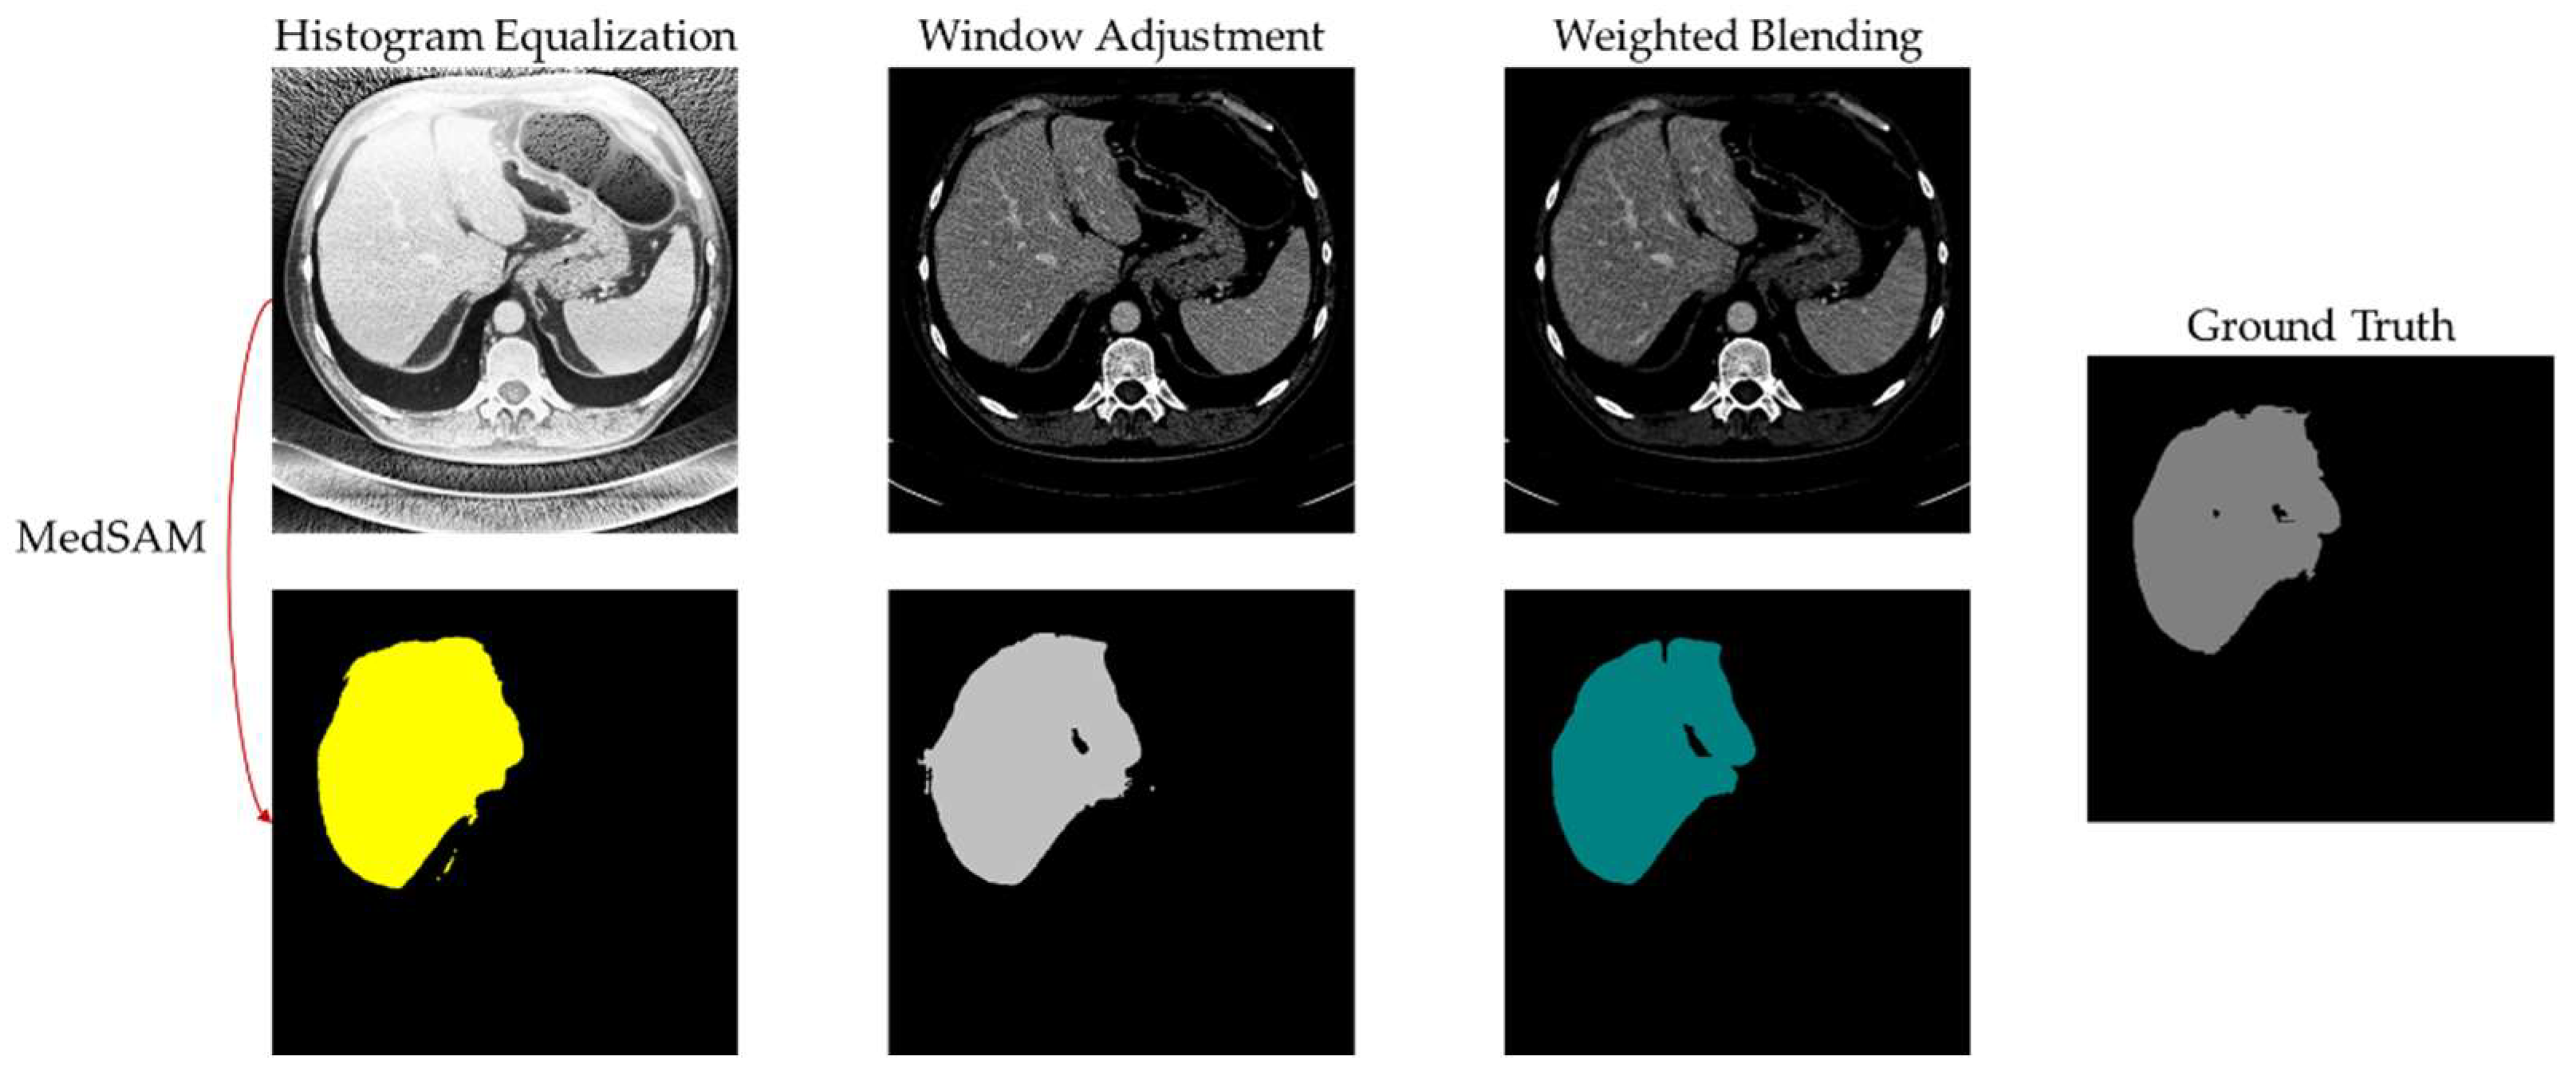

- Digital image enhancement strategies for medical image features: Medical images often contain a high level of noise and details hidden in low-intensity regions. To address this, anisotropic diffusion filters are used for denoising, and histogram equalization is employed to enhance the texture and details of medical images globally. Additionally, the fusion of window level and window width adjustment techniques specific to medical images is applied to target the regions of interest within the image. These strategies aim to achieve global enhancement of medical images while highlighting the desired targets.

4.6. Experimental Results and Analysis

5. Discussion